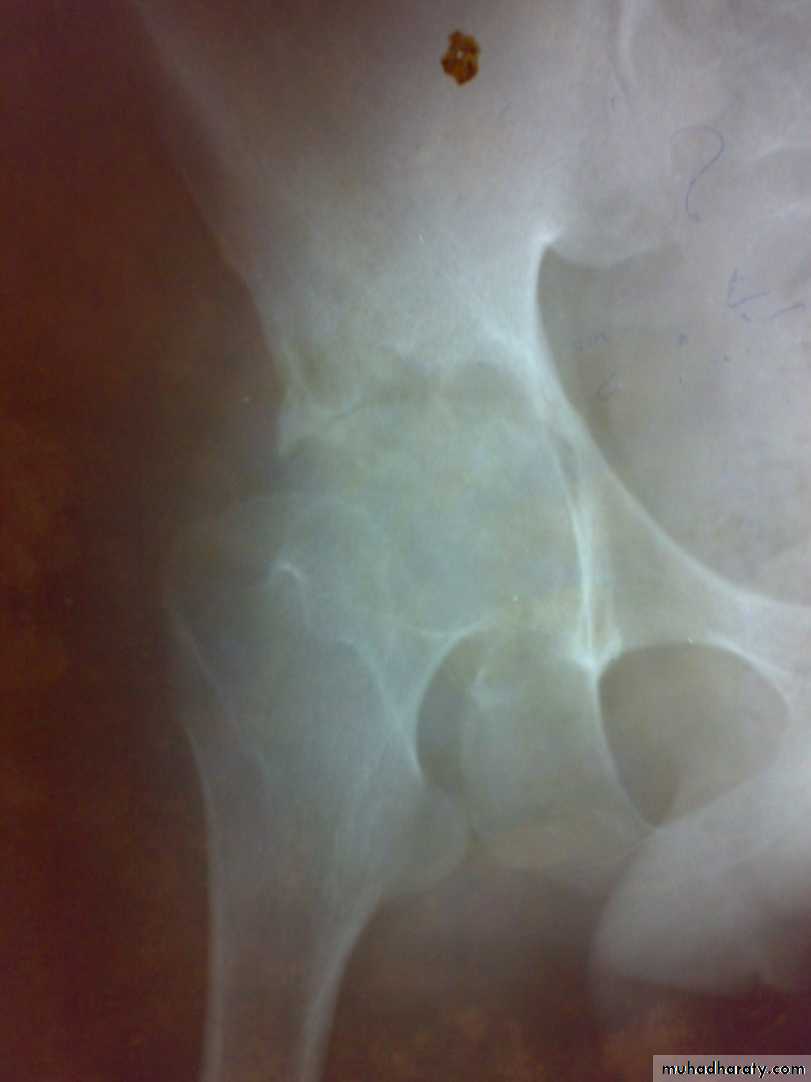

Radiological features

early changes:

Soft tissue swelling, Periarticular osteoporosis

Loclized osteoprosis (Bone ends ‘washed – out’ or localized decalcification ).

Narrowing and irregularity of the articular ends.

Late changes:

Erosions of the subarticular cartilage.

cystic changes appeared.